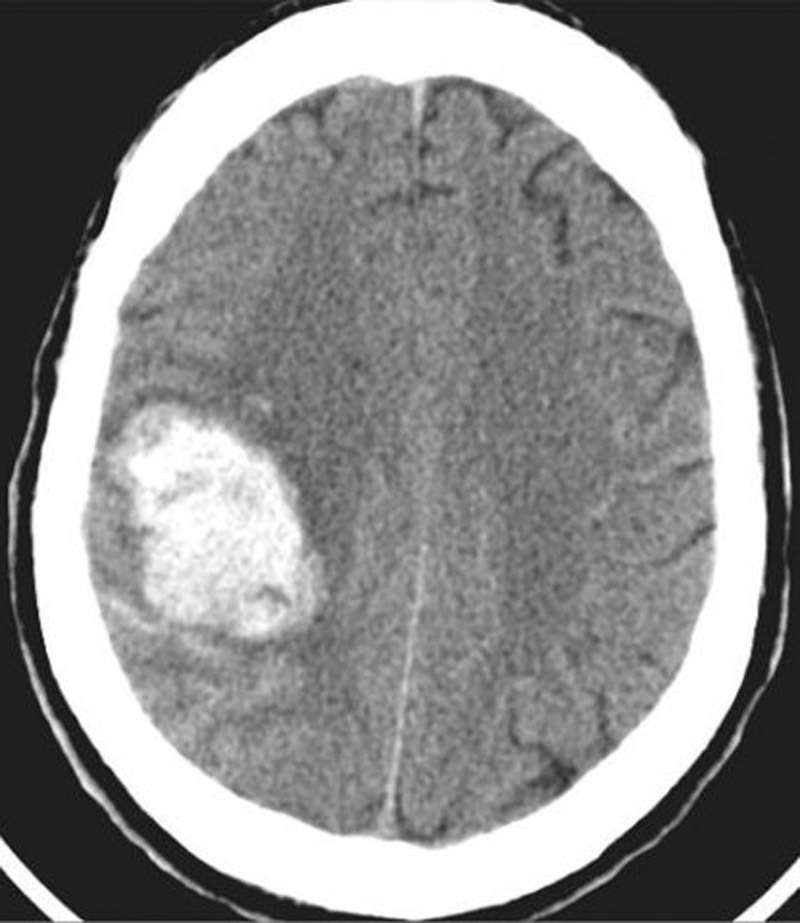

Il s’agit d’un hématome cortical sur une coupe TDM cérébrale sans injection. L’hémorragie apparaît comme une zone spontanément hyperdense. Ici il s’agit d’une hyperdensité spontanée frontale droite. Il s'agit bien d'un hématome frontal car en avant du sillon de Rolando, qui, sur des coupes axiales, souvent obliques, est en général situé assez en arrière sur ces coupes hautes.